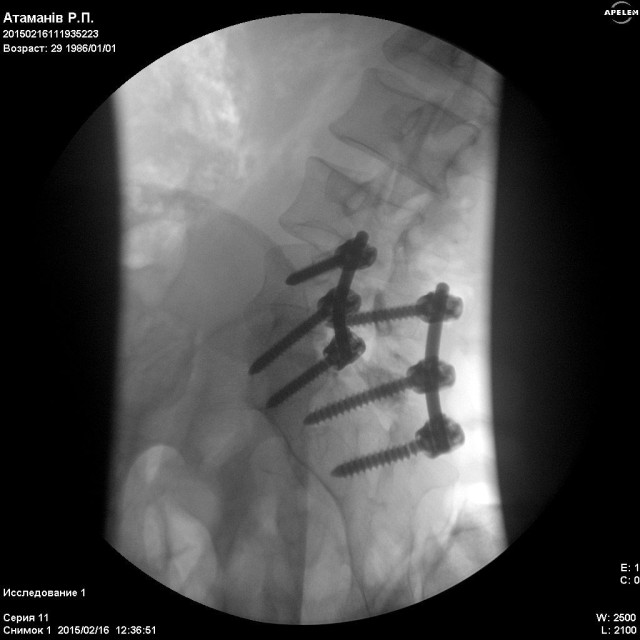

У Харківському державному інституті патології хребта і суглобів ім. проф. М.І. Сітенка, Сергію зробили операцію відкритого вправлення Л5 хребця. Та провели стабілізацію на рівні Л4,Л5-С1, конструкцією "медтронік". Тобто йому зафіксували хребет за допомогою металевих з'єднань.